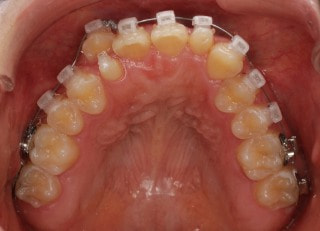

治療前